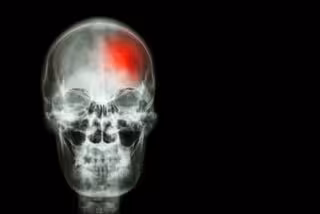

Hallan un nuevo tratamiento para el ictus "muy prometedor"

Ictus, cerebro, cerebrovascular

GETTY//STOCKDEVIL - Archivo